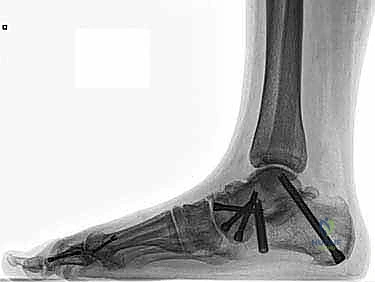

عندما يكون القرار الطبي هو التدخل الجراحي، فإن المرضى بين يدي الأستاذ الدكتور محمد هطيف يحظون بأعلى مستويات الرعاية الطبية المتاحة في اليمن. تُجرى هذه العملية المعقدة باستخدام تقنيات الجراحة المجهرية (Microsurgery) لضمان الدقة المتناهية، وغالبًا ما تُدمج مع استخدام مناظير المفاصل بدقة 4K لمعالجة أي إصابات غضروفية داخلية دون الحاجة لفتح المفصل بالكامل.

* الإصلاح المباشر (Direct Repair): إذا كانت أنسجة الرباط الممزقة ذات جودة جيدة (عادة في الإصابات الحديثة)، يقوم الدكتور هطيف بخياطتها مباشرة. يستخدم خطاطيف تثبيت عظمية (Suture Anchors) صغيرة جداً ومصنوعة من مواد متوافقة حيوياً (تذوب مع الوقت أو من التيتانيوم) لغرس الخيوط القوية في عظمة الكعب الإنسي، ثم يتم سحب الرباط الممزق وتثبيته بقوة في مكانه التشريحي الأصلي.

- إعادة البناء (Reconstruction): في الحالات المزمنة حيث يكون الرباط الأصلي قد تليف، تآكل، أو أصبح غير كافٍ للاستخدام، يلجأ الدكتور هطيف إلى تقنية "إعادة البناء". تتضمن هذه التقنية المتقدمة استخدام رقعة وترية (Graft)، إما من جسم المريض نفسه (Autograft - مثل أوتار الركبة أو وتر من القدم) أو رقعة صناعية متطورة. يتم حفر أنفاق ع